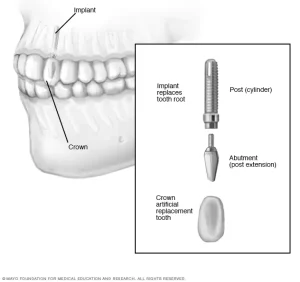

وزراعة الأسنان هي عبارة عن أعمدة معدنية أو إطارات يتم وضعها جراحياً في عظم الفك أسفل اللثة.

عندما توضع في مكانها، فإنها تسمح لطبيب الأسنان الخاص بتركيب الأسنان البديلة عليها

زراعة الأسنان عبارة عن غرسة من التيتانيوم تأخذ شكل جذر السن الاسطواني ويتم تثبيت دعامة فوقها لتحمل تاج السن او جسر او حتى طقم الأسنان الكامل.

الدعامات تتكون من التيتانيوم او من مادة الزركونيوم

أما التيجان والجسور فتكون من البورسلين او الزركونيوم او الأكريليك

او يقوم طبيب الأسنان بعمل أي نوع من تركيبات الأسنان وتثبيتها بالبراغي على الدعامات.

وتأتي زراعات الأسنان بتصميمات كثيرة لكن التصميم الأكثر شيوعا الان هو الشكل الاسطواني المدرج للأسفل المشابه لجذر الأسنان الطبيعي

وعند تصنيعها تعدل الزراعة بإضافة خصائص وتصميم متناهي الصغر ليساعد العظم على عملية الالتئام معها

فهناك نوعان شائعان في زراعة الأسنان، وهما الغرسات الباطنية والغرسات تحت العظم.

الغرسات الباطنية يتم زرعها جراحياً مباشرة في عظم الفك، بمجرد أن تلتئم أنسجة اللثة المحيطة ، يلزم إجراء عملية جراحية ثانية لتوصيل منشور بالزرع الأصلي.

أخيراً، يتم ربط السن، أو الأسنان، الصناعية بالآخر بشكل فردي، أو مجمعة على جسر أو طقم أسنان.

أما الغرسات تحت العظم تتكون من إطار معدني مثبت على عظم الفك أسفل أنسجة اللثة.

عندما تلتئم اللثة، يصبح الإطار ثابتاً على عظم الفك.

التثبيتات، التي تعلق على الإطار ، تبرز من خلال اللثة.

كما هو الحال مع الغرسات البطانية، يتم بعد ذلك تثبيت الأسنان الصناعية .